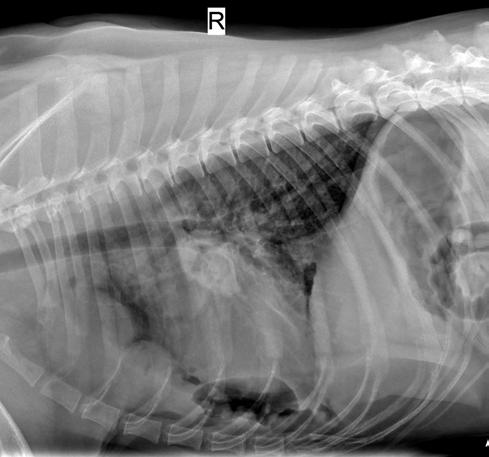

Se realiza radiografía de tórax (Fig. 1) que revela car-

diomegalia generalizada severa, índice de Buchanan de 15 cuerpos vertebrales, que puede corresponder a un severo aumento de las cámaras cardiacas, o a la presencia de líquido pericárdico. Se observa, además, un patrón pulmonar intersticial perihiliar, compatible con edema pulmonar, foco de neumonía o hemorragia pulmonar.

M. López,1 V. Fernández,2 J. Engel3 1Servicio de cardiología y diagnóstico por imagen. 2Servicio de cirugía. Laclinicaveterinaria. c/Marroquina 26. 28030 Madrid. 3Servicio de cardiología. ANICURA-Benipeixcar Hospital Veterinario. Avinguda de la Constitució 68, bajo izq. 46009 Valencia. ANICURA-San Francisco Hospital Veterinario. c/ Sant Francesc 65. 12500 Vinaròs (Castelló). ANICURA-San Vicente Hospital Veterinario. c/ Veterinario Manuel Isidro Rodríguez García 17. 03690 San Vicente del Raspeig (Alicante). Figura 1. Radiografía lateral de tórax en la que se observa cardiomegalia generalizada, VHS 15. Patrón alveolar intersticial compatible con edema pulmonar. Patrón vascular mixto y patrón bronquial en lóbulos caudales, compatible con bronquitis crónica, mineralización por degeneración senil.

En el caso que presentamos podemos confirmar cardiomegalia severa y edema pulmonar dado que el estudio radiológico del tórax permite establecer el tamaño cardiaco y valorar el patrón pulmonar. La insuficiencia cardíaca congestiva izquierda se caracteriza por un patrón intersticial, que puede evolucionar a patrón alveolar en la región perihiliar que tiende a distribuirse hacia caudodorsal, característico del edema pulmonar cardiogénico, patrón vascular venoso.